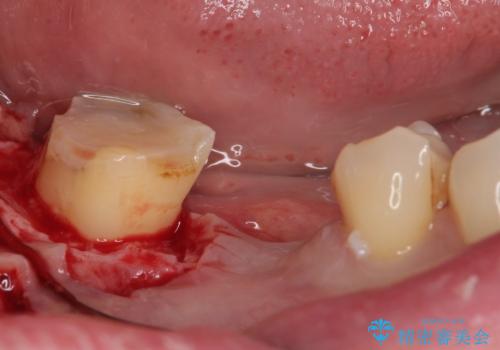

診察より、奥から2番目の歯が割れている可能性が非常に高いため、まずは奥から2番目の歯の状態を診断することとしました。

クラウンを外したところ、目視でも確認できる破折線が認められたため、抜歯することとしました。